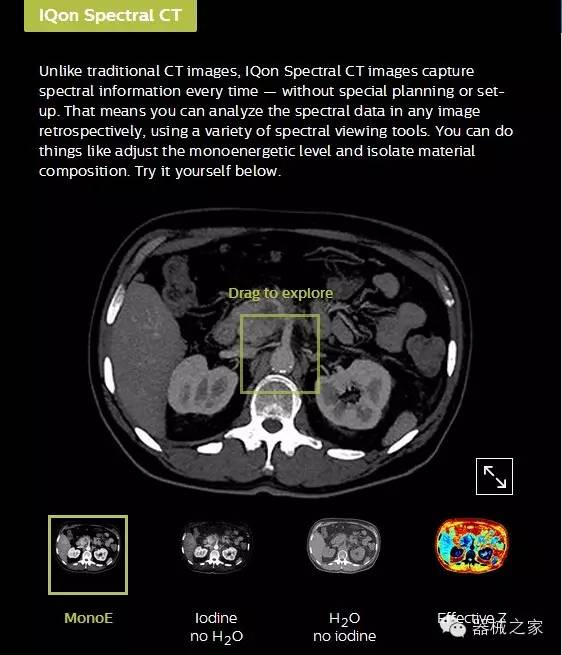

IQon光譜CT能夠按照需求提供光譜量化和工具,并能通過簡單工作流程、在低劑量下對結(jié)構(gòu)進(jìn)行定性分析

IQon光譜CT -- 是業(yè)界首臺以探測器為成像基礎(chǔ)的光譜CT,它可以在單次常規(guī)掃描下獲得傳統(tǒng)解剖影像及光譜功能影像。不僅可以提供精準(zhǔn)的診斷信息,還可簡化工作流程、在低劑量下完成定量與定性分析。